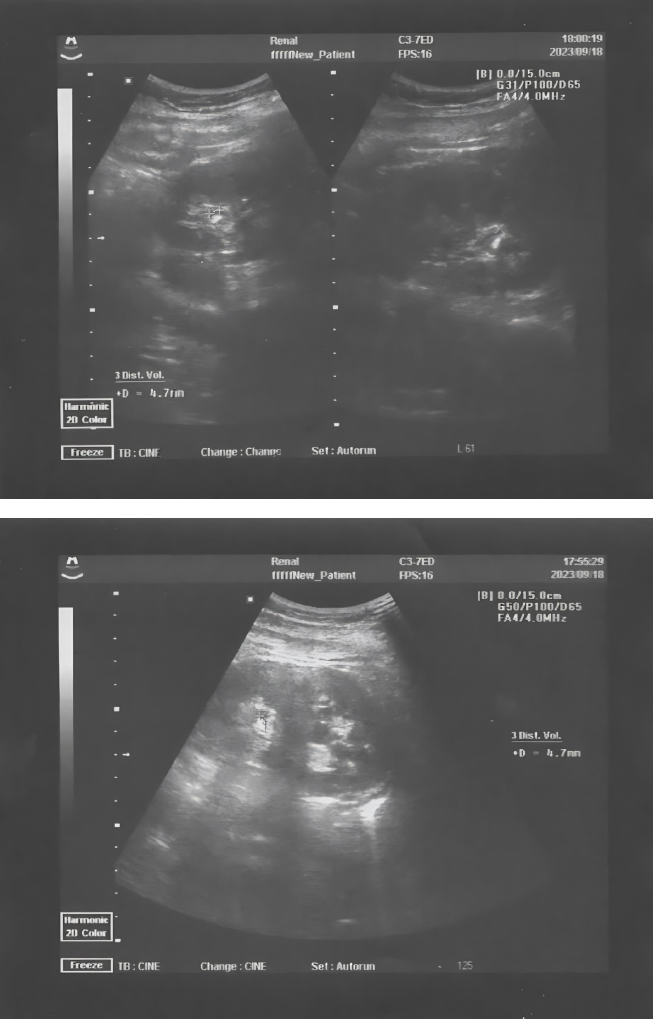

Instrumental studies. Ultrasound examination of the kidneys and bladder dated September 20th, 2023 (Figs. 1 and 2):

- Right kidney: size 10.2 ´ 4.2 cm, location is normal, contours are smooth, pelvicalyceal system (PCS) is not expanded, ratio of PCS to parenchyma is normal. Additional signs: a microlith in the upper calyx – 4 ´ 3 mm; a microlith in the lower calyx – 3.5 ´ 3 mm with shadowing. Area of adrenal glands without specific features.

- Left kidney: size 10.5 ´ 4.6 cm, normal location, smooth contours, PCS expanded and deformed (pelvis – 1.6 cm, calyx – 0.8 cm), ratio of PCS to parenchyma is normal. Additional signs: a microlith in the upper calyx, triangular shape, 4.2 ´ 2.0 mm with shadowing; a microlith in the lower calyx – 2.5 ´ 3 mm with shadowing. The lower third of ureter on the left expanded to 0.4 cm with the presence of internal structures in the form of a hyperechoic formation sized 7.0 ´ 4 mm with shadowing at 2.2 cm from the ureteral orifice. Discharge from the orifice on the left is slowed and weakened.

Fig. 1. Patient G. Ultrasound of the kidneys from September 20th, 2023. The presented images show microliths in the upper and lower calyces of the right and left kidney

Conclusion: Ultrasound-signs of concretion in the lower third of the ureter on the left, concretions of both kidneys, urostasis on the left.

It should be noted that several microliths had already been detected in the patient compared to the data of June, 2023. This indicated a rapid progression of urolithiasis.